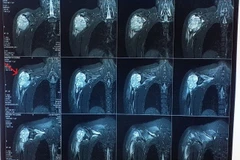

Bệnh nhân Nguyễn Thị C (sinh năm 1987, trú tại Cà Mau) nhập viện ngày 30/6 trong tình trạng sưng u mỏm xương tay vai phải, tay phải tê bì mất chức năng cầm nắm.